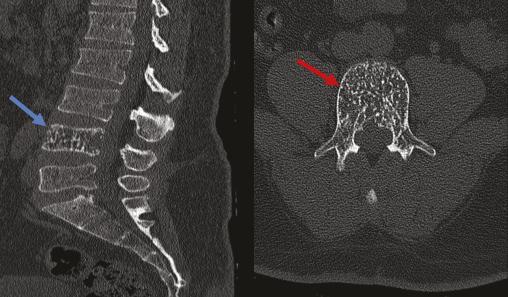

Un homme âgé de 42 ans, sans antécédents notables, souffre depuis un an de lombosciatalgies bilatérales d’aggravation progressive, avec installation, depuis trois jours, de troubles génitosphinctériens à type de rétention urinaire évoluant dans un contexte d’apyrexie et de conservation de l’état général. À l’examen clinique, le patient est conscient, stable sur le plan hémodynamique et respiratoire. L’examen neurologique objective une parésie des deux membres inférieurs avec des réflexes ostéotendineux vifs. Une imagerie par résonance magnétique (IRM) médullaire, réalisée en urgence, met en évidence une lésion de la quatrième vertèbre lombaire en hypersignal T1 et STIR, de signal hétérogène en T2, se rehaussant après injection du produit de contraste avec une épidurite antérieure en regard, responsable d’une compression du fourreau dural (fig. 1). Un complément scanographique sans injection de produit de contraste, réalisé par la suite, objective la lésion ostéolytique du corps vertébral de L4, avec un aspect piqueté épais d’os dense (en têtes d’épingle) sur la coupe axiale et grillagé sur la reconstruction sagittale, faisant évoquer un hémangiome osseux agressif (fig. 2). Le patient a bénéficié en urgence d’une laminectomie lombaire en regard de L4, avec une bonne amélioration clinique.

Les hémangiomes vertébraux sont des tumeurs bénignes le plus souvent asymptomatiques. Ils sont rarement agressifs (moins de 1 % des cas),1 touchent l’adulte entre 40 et 60 ans, avec une prédominance féminine.1 La localisation dorsale est la plus fréquente, suivie par l’atteinte lombaire.2 Le tableau clinique est celui d’une compression médullaire et/ou radiculaire secondaire à une extension progressive de l’hémangiome dans le canal vertébral.1 La radiographie standard, souvent réalisée en première intention, montre une lésion osseuse lytique renfermant des trabécules verticales (signe en velours côtelé). L’imagerie en coupe (tomodensitométrie [TDM] et IRM) occupe une place primordiale dans le diagnostic positif. Le scanner objective l’hémangiome osseux sous forme d’une lésion osseuse mixte sclérotique renfermant de la graisse avec visualisation des trabéculations verticales réalisant un aspect piqueté épais d’os dense (en têtes d’épingle) sur la coupe axiale et grillagé sur la reconstruction sagittale.3 À l’IRM, l’aspect des hémangiomes varie en T1 en fonction de la quantité de graisse, la perte de l’hypersignal T1 est un des critères d’agressivité de l’angiome, ils sont visibles en hypersignal T2, et le rehaussement est souvent présent. L’IRM permet également de mettre en évidence une épidurite et la compression médullaire ou radiculaire.3 Les caractères d’agressivité de l’hémangiome sont une localisation entre la 3e et la 10e vertèbre dorsale, l’atteinte de l’ensemble du corps vertébral, l’extension à l’arc postérieur, l’aspect discontinu des corticales, l’extension dans les parties molles paravertébrales ou intracanalaires à l’IRM. En cas de doute diag­nostique, l’examen anatomopathologique reste la référence. La prise en charge repose sur un geste de décompression en ­urgence, précédé, si possible, par une embolisation. La vertébro­plastie peut être associée en cas de syndrome vertébral douloureux.